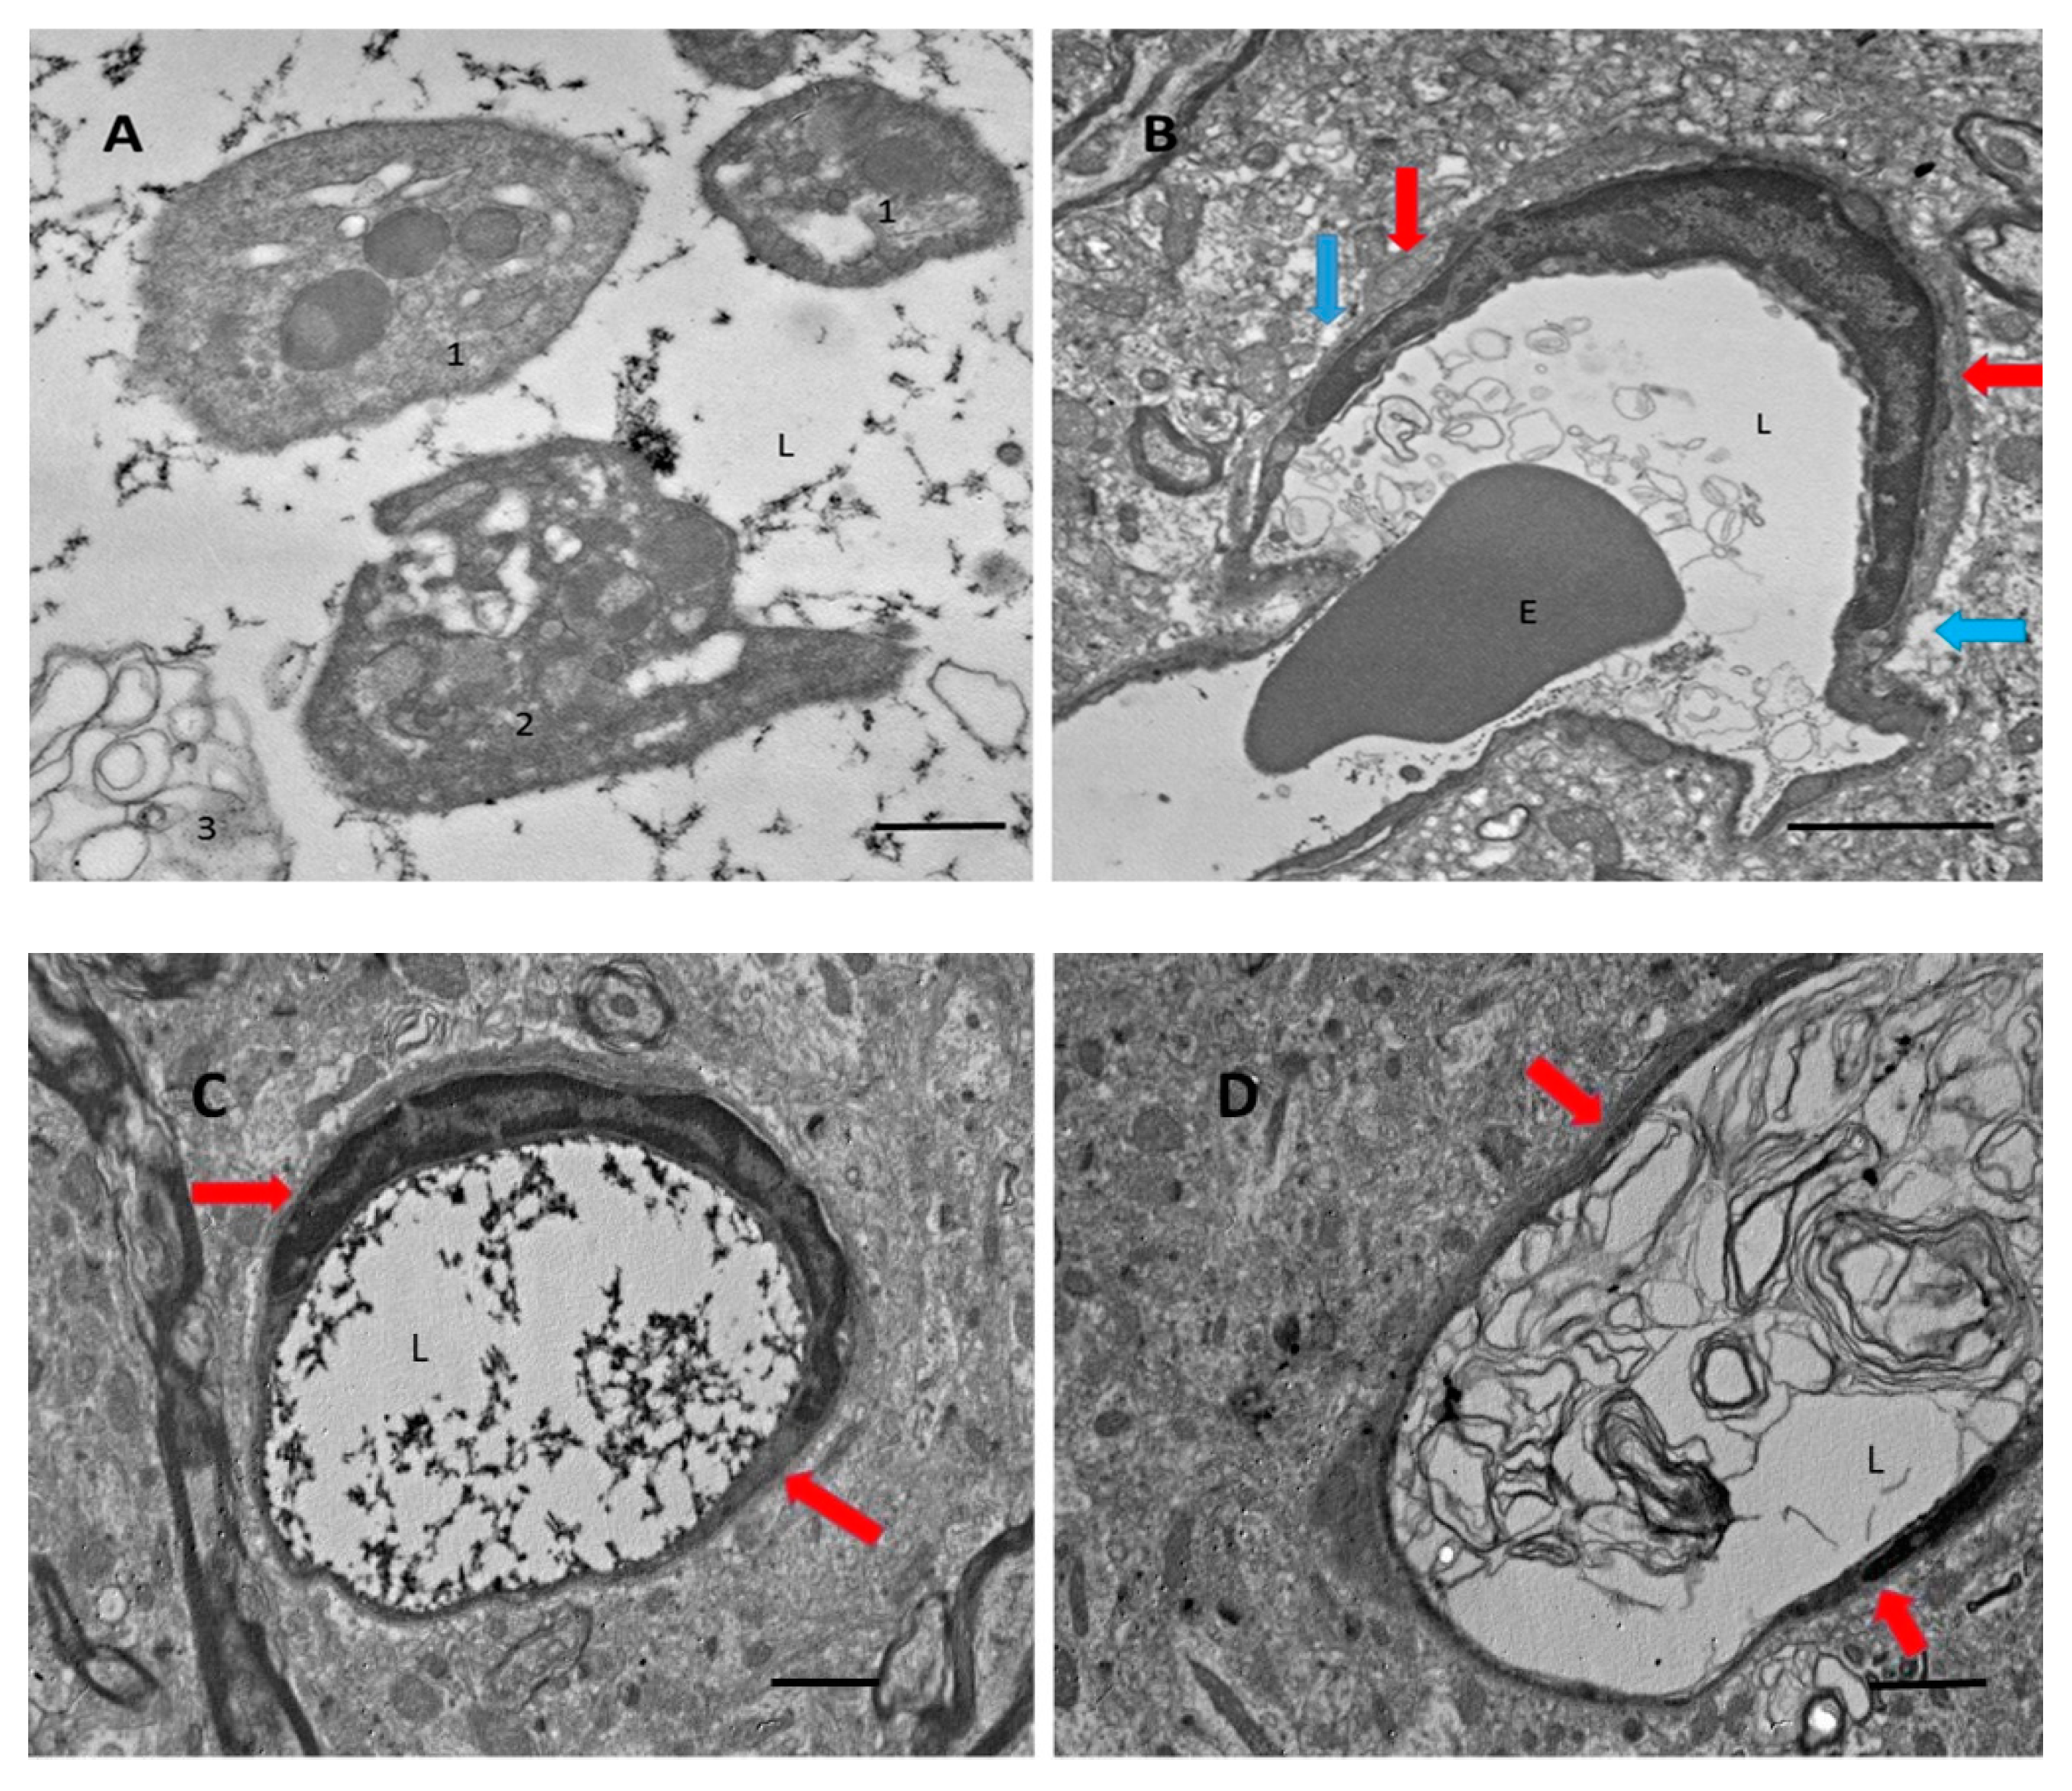

Previously, we found that there is a massive release of Aβ during thrombosis [8]. In this study, we used electron microscopy to analyze blood vessels within the affected areas of the brain after ischemic stroke, and we looked for characteristic signs of coagulation. We found that vessels, especially small vessels, are filled with clot-related elements, such as fibrin strands (Figure 1A,C), clot-related debris (Figure 1B,D), and different forms of platelets (Figure 1A). Platelets also showed clot-related morphological conversions, from a relatively rounded form (Figure 1A, “1”), to stellate (Figure 1A, “2”), and then to a fully degranulated form (Figure 1A, “3”). Fibrin strands fill the majority (≈60%) of blood vessels in the ischemic zone (Figure 1C, also at high magnification in Figure 1A). Many vessels are also filled with debris that looks like lipid membrane bubbles (Figure 1B,D). Astrocyte endfeet, which envelop blood vessels walls in many cases, appear swollen (Figure 1, blue arrows), whereas basal membranes in perivascular spaces are expanded in volume (Figure 1, red arrows).

Figure 1.

Blood vessels after transient middle cerebral artery occlusion (tMCAO) under the electron microscope. (A) Platelets, rounded and stellate (see text). (B) Erythrocyte (E) entrapped in debris. (C) Fibrin strands in the vessel lumen (L). (D) Significant swelling and vacuolar bubbles in the astrocyte endfeet around the blood vessels (blue arrows). Perivascular space (red arrows). Scale bars: (A), 500 nm; (B), 2 µm; (C,D), 600 nm.

After we confirmed by electron microscopy that coagulation is present in the area affected by ischemia, and based on our previous research showing massive generation of Aβ peptides during photocoagulation, we hypothesized that Aβ might also be generated in damaged blood vessels after monofilament-induced ischemia.

The present work established the presence of Aβ peptide in the ipsilateral part of the brain after tMCAO. Using electron microscopy, we also confirmed that in the damaged brain regions following tMCAO, the majority of small blood vessels showed signs of coagulated blood within and showed a clear swelling of astrocyte endfeet surrounding the blood vessels. This coagulation could be a source of Aβ, as was proposed elsewhere (see review in [2]). Blood coagulation produces massive amounts of Aβ peptides from the amyloid precursor protein (APP) liberated from platelets during experimental photothrombosis of brain blood vessels [8] and during experimental thrombosis of blood vessels in the skin [9] (Figure 1A–D). Aβ peptides are abundantly accumulated on the walls of small blood vessels, most likely on the external walls (Figure 2A,B), in some capillaries, and probably in astrocyte endfeet (Figure 2A). Our experiments showed that Aβ is present mainly in its non-aggregated form, which is recognized by a specific anti-Aβ-antibody, whereas only a small amount of aggregated Aβ, which is stained with Congo red, was detected in the form of isolated extracellular plaques (Figure 2A, panel 1, green spots).